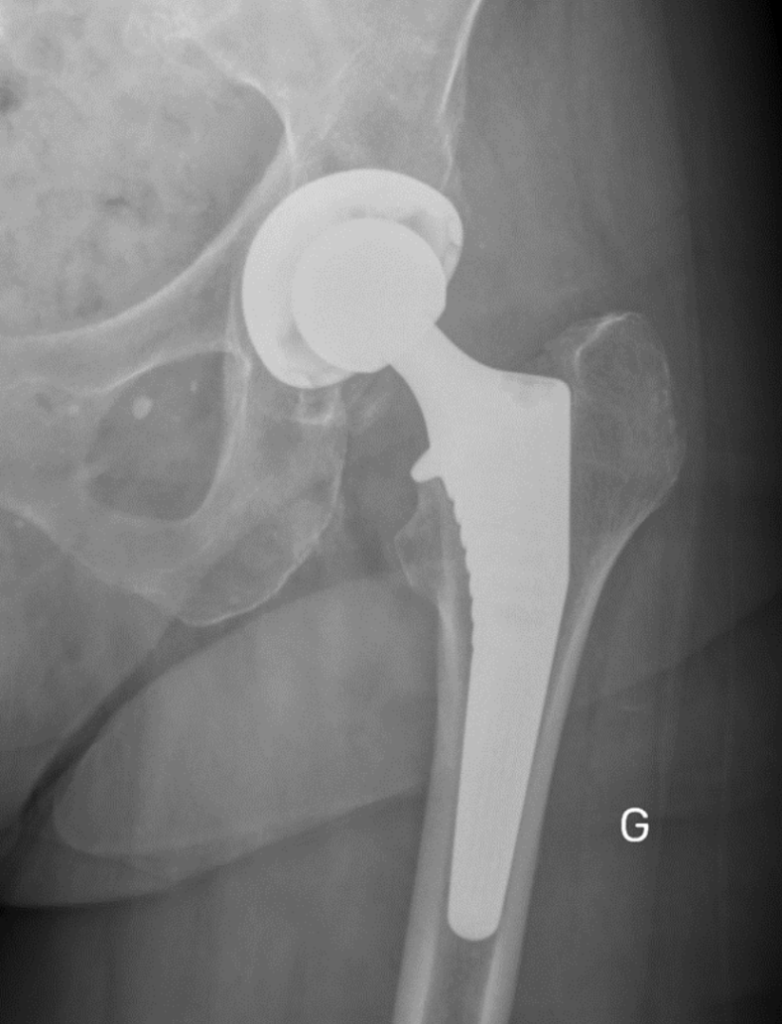

Le diagnostic de la nécessité d’une prothèse de hanche est établi par un examen clinique approfondi, des radiographies et éventuellement d’autres examens d’imagerie. Le Dr Gastaud évaluera votre condition médicale pour déterminer si une prothèse de hanche est appropriée.

7. Descellement et usure de la prothèse

• Qu’est-ce que c’est ?

• Le descellement ou l’usure de la prothèse sont des complications tardives, généralement liées à l’usure de la prothèse après de nombreuses années.

• Quelle est la durée de vie d’une prothèse de hanche ?

• En moyenne, une prothèse de hanche dure entre 20 et 25 ans, mais cette durée peut varier en fonction de l’âge du patient et de son niveau d’activité physique.